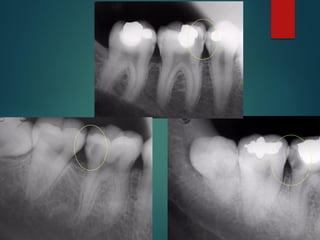

Clasificación

Radiográfica De las

Caries

 Incipiente de esmalte

 De esmalte

 Dentinaria superficial

 Dentinaria profunda

 Sobreproyectada en cámara pulpar

 Penetrante

Clasificación Radiográfica

De Las Caries